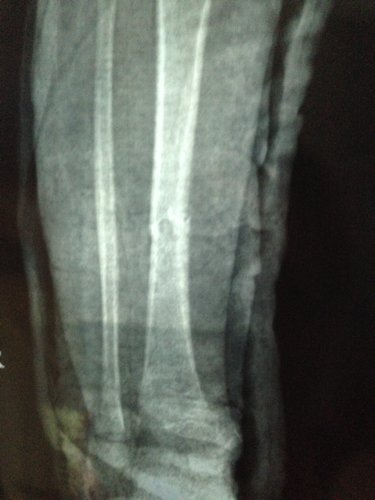

男孩三周岁 5-9 被电动车撞,右小腿胫骨骨折,正位对线良好,侧位错位三分之一。现差不多六周,前两天腿甩痛了就近急诊拍片,医生说骨头在长的,一周后把石膏拆掉吧,否则肌肉萎缩影响走路的,请各位医生指点一下,错位情况下,石膏拆了会影响恢复吗?因为两段骨头没合上阿,我上传一张之前的片子,请大家帮忙看一下。